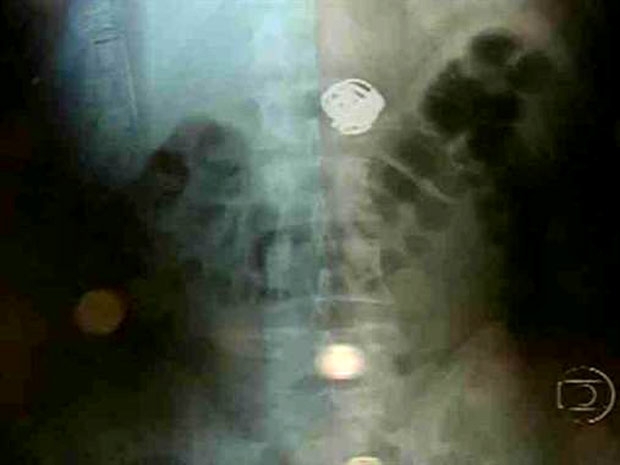

Joias foram retiradas do corpo de assaltante na tarde desta segunda-feira (Foto: Reprodução/TV Globo Nordeste)

Joias ficaram alojadas perto do esôfago de um assaltante (Foto: Reprodução/TV Globo Nordeste)

Segundo informações do hospital, foram retirados dois anéis, uma corrente e um cordão de ouro. O procedimento foi demorado por conta da dificuldades dos médicos em localizar o ponto exato onde as joias estavam. Uma delas se alojou próximo ao esôfago. O assaltante segue internado e, assim que receber alta, vai voltar para a carceragem do Cotel.